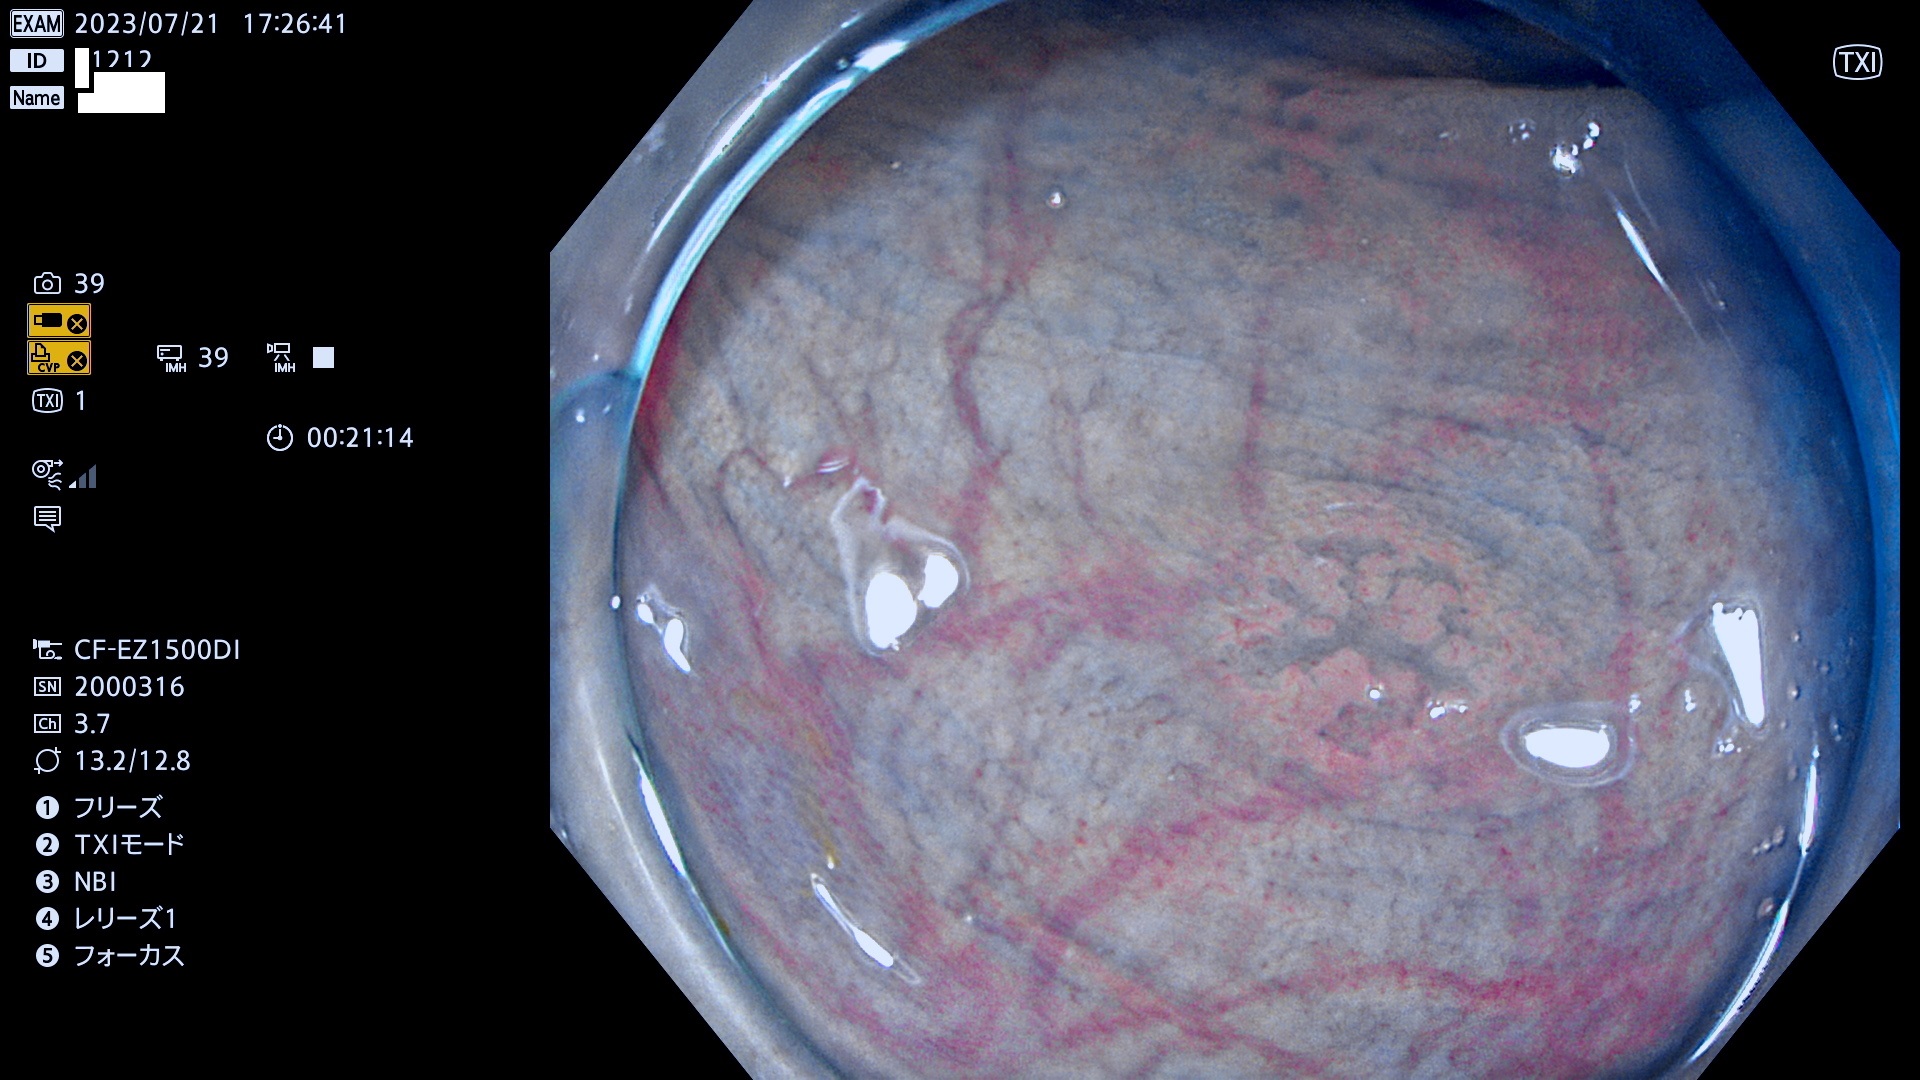

「表面型腺腫(Flat Adenoma)の中で、完全に平坦な物をUb、陥凹している物をUcと呼びます。平坦隆起型(Ua)よりも、発見が難しく危険な病変です。このタイプは「内視鏡後・大腸癌の重要犯人」であり、この発見率は「腺腫発見率」よりも、重要な意味があります。

抽出の対象期間 2023年7月20日(木)〜7月23(日)の4日間(48件の検査)12件